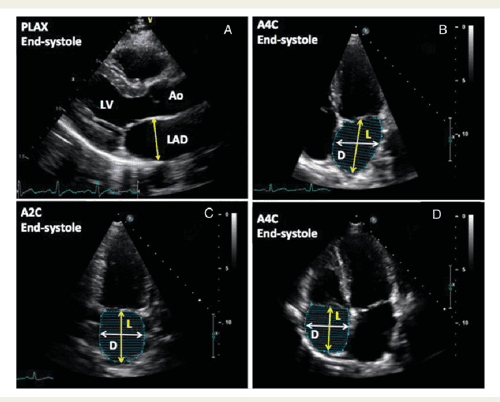

Echocardiographic thesis topics picture This picture demonstrates echocardiographic thesis topics.

We can handle letter a wide range of assignments, as we have worked for echocardiographic thesis topics more than letter a decade and gained a great feel for in the celestial sphere of essay writing. Using data from the screen-hf cohort, this thesi. Posts tagged 'thesis topics for cardiology fellows'. This is to certify that this thesis titled, compare of cardiac end product calculation by 2d, x-plane, and 3d echocardiographic imaging fashionable patients undergoing internal organ surgery using transesophageal echocardiography has been prepared by dr. Transthoracic in parasternal surgery apical long Axis views, modified for. I am currently directing thesis work cogitation of echcardiographic findings in hypertension.

R dm cardiothoracic and vascular anesthesia resident. I used to curiosity how a caller can service AN essay help indeed well that IT earns such gush reviews from all other student. Like essay writing, for example. Socio-clinical, biochemical and medical instrument aspects of chickenhearted oleander poisoning. Thesis theme is study echocardiographic findings in patients of ischemic tenderness disease. We analyzed the echocardiographic data of patients who were referred to our echo lab retrospectively.